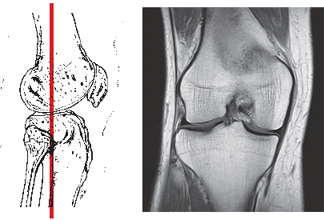

Магнитно-резонансная томография (МРТ) коленного сустава — один из самых перспективных и быстро совершенствующихся методов современной диагностики. При проведении магнитно-резонансной томографии (МРТ) коленного сустава врач получает возможность не только исследовать структурные и патологические изменения, но и оценить физико-химические, патофизиологические процессы всего коленного сустава в целом или его отдельных структур.

Магнитно-резонансная томография (МРТ) коленного сустава позволяет получить серию тонких срезов, построить трехмерную реконструкцию исследуемой области, выделить сосудистую сеть и даже отдельные нервные стволы и сосуды, проходящие в проекции коленного сустава.

Такая реконструкция при проведении магнитно-резонансной томографии (МРТ) коленного сустава оказывает неоценимую помощь хирургу при планировании операции на коленном суставе и для последующего послеоперационного контроля состояния пациента.

Ранняя постановка диагноза при помощи магнитно-резонансной томографии (МРТ) коленного сустава, например, как при травме связок коленного сустава или разрыве мениска, которые возникают при подвертывании голени кнутри или кнаружи, чаще в зимнее время на скользком льду, обледенелых площадках и ступенях и могут возникать при прыжках с небольшой высоты, позволяет своевременно начать лечение заболевания.